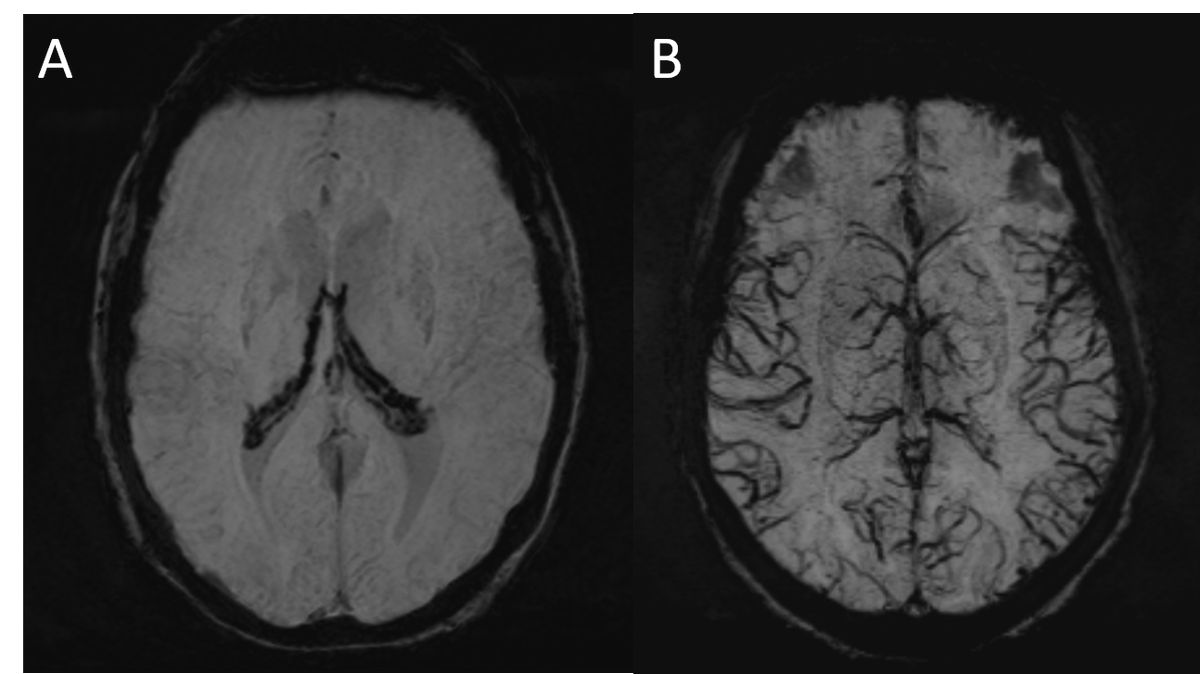

[NeuroradNuggets] Two incidental intriguing SWI images. Both are related to chronic anemia. Guess what happened?

ShengChe's tweet image. [NeuroradNuggets]

Two incidental intriguing SWI images. Both are related to chronic anemia. Guess what happened?